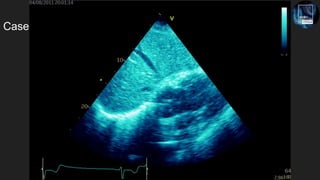

The document discusses the potential of echocardiography in managing cardiac arrest, emphasizing its non-invasive and painless nature for bedside assessments. It highlights the importance of recognizing the causes of cardiac arrest, such as hypovolaemia and tension pneumothorax, and the need for proper training of healthcare staff. Additionally, it provides resources for further learning, including social media and a dedicated website.